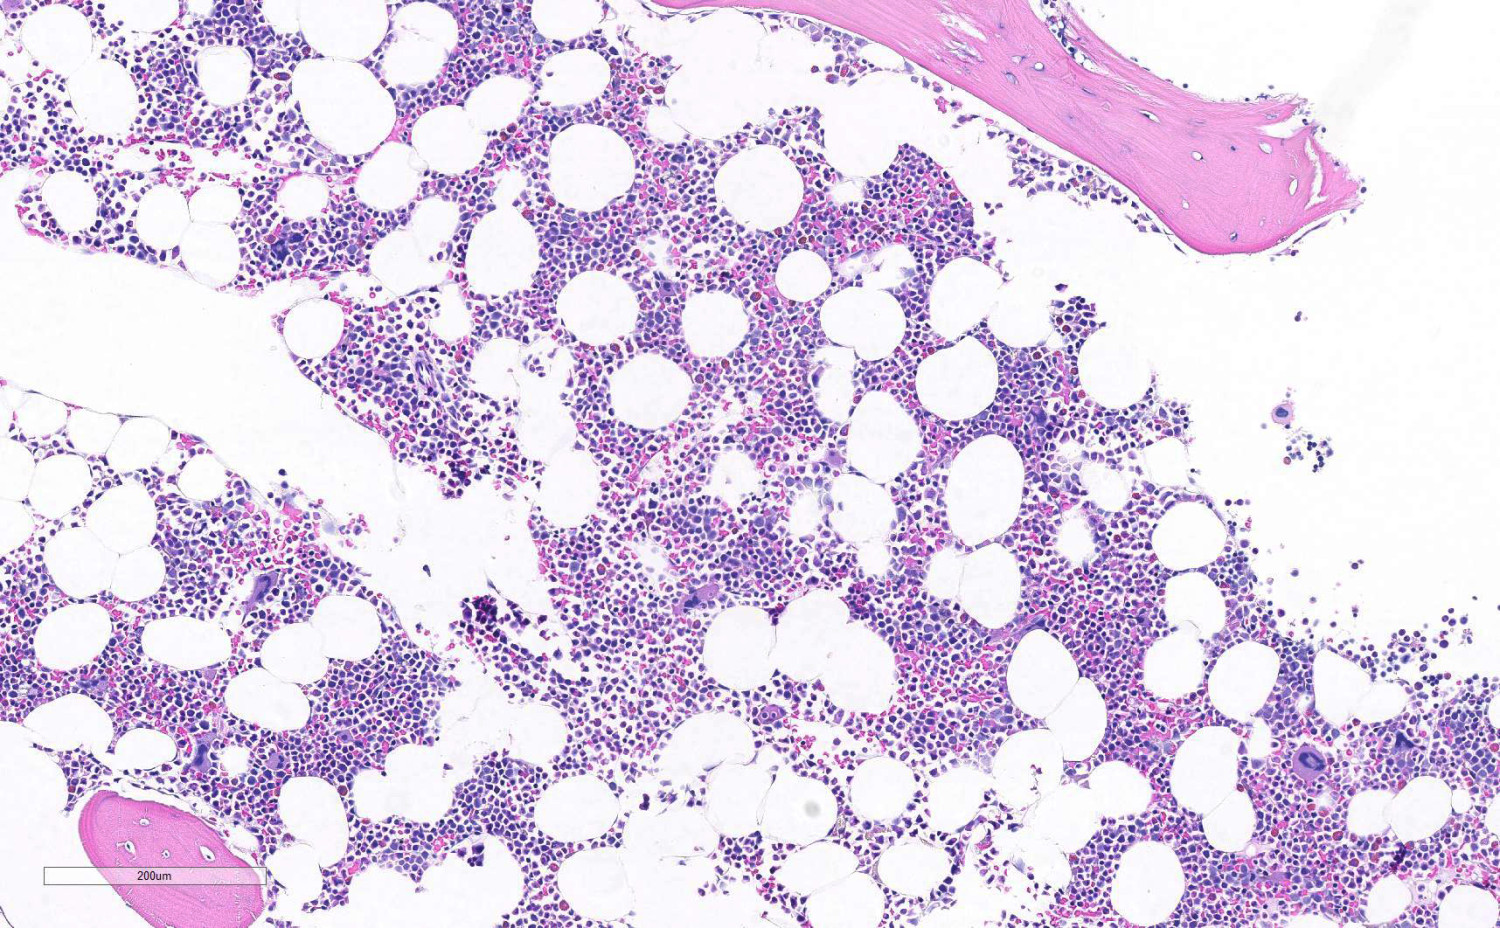

Det finnes ingen enkel test for å stille diagnosen (6). I praksis vil den først bli aktuell etter at man har tatt en benmargsbiopsi. Sammenlignet med normal benmarg (figur 1) vil man ved aplastisk anemi finne uttalt hypoplasi av hematopoese, og margrom domineres av fettceller (figur 2). I biopsien kan man samtidig vurdere om det foreligger annen primær malign benmargssykdom, lymfoproliferativ sykdom, metastaser, inflammatoriske eller infeksiøse prosesser eller tilstand med økt produksjon av blod, som ved hemolytisk anemi (figur 3).